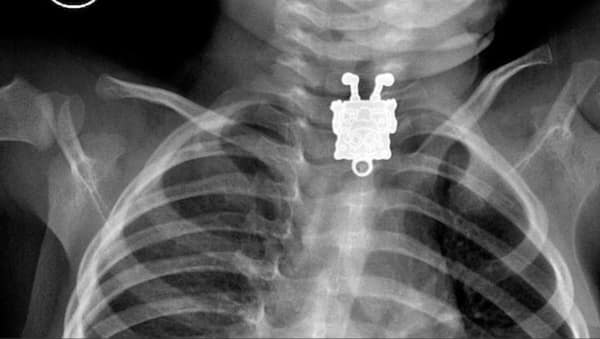

Weird xray photos

I used to think that nothing could surprise me anymore—until I stumbled upon some weird x-ray photos that made me reconsider my stance on human ingenuity (or lack thereof). Apparently, some people have a knack for getting objects lodged where they absolutely shouldn’t be. If you’ve ever wondered how not to use everyday items, these images might provide some unintended guidance.

This collection showcases 31 bizarre x-ray images that defy logic and anatomy textbooks alike. Each photo reveals unexpected objects making cameo appearances inside the human body, turning medical imaging into a gallery of the absurd. From common household items inexplicably found in unusual places to anomalies that would leave even seasoned doctors scratching their heads, these images offer a perplexing glimpse into the more “creative” side of medical emergencies. They highlight the intersection of curiosity, misadventure, and perhaps a dash of poor decision-making, all captured through the lens of radiology.